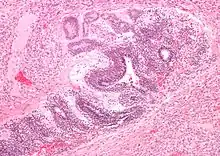

Micrograph of the primitive neuroepithelium of an immature teratoma of the mediastinum. H&E stain. | |

The mediastinum has three main parts: the anterior mediastinum (front), the middle mediastinum, and the posterior mediastinum (back). Masses in the anterior portion of the mediastinum can include thymoma, lymphoma, pheochromocytoma, germ cell tumors including teratoma, thyroid tissue, and parathyroid lesions. Masses in this area are more likely to be malignant than those in other compartments.[2][3]